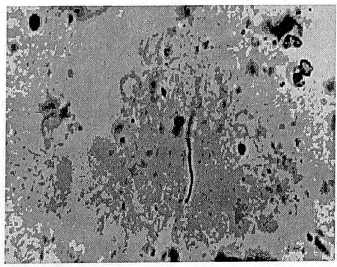

Рис. 2. Гнойный мембранит с вовлечением в воспалительный процесс амниона. Окраска гематоксилином и эозином. х 350.

Гистологические признаки воспаления, возникающие при поражении тканей последа различными условно-патогенными микробами оказались весьма сходными. Этим было обусловлено суммарное описание выявленных изменений. Патоморфологическая картина хориоамнионита характеризовалась преимущественно диффузной инфильтрацией полиморфноядерными лейкоцитами ткани плаценты и плодных оболочек (рис. 1,2), а в некоторых случаях участками некрозов и микроабсцессов (рис. 3,4). Чаще всего воспалительные инфильтраты локализовались в хориальной пластинке, базальной пластинке, амнионе, периваскулярном отделе стромы крупных ворсин и интервелезном пространстве. Наряду с воспалительными изменениями в 36,3% наблюдений отмечены инволютивно-дистрофические и дисциркуляторные нарушения.